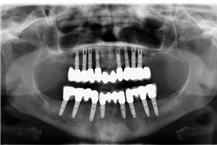

מרפאת השיניים הפרטית של ד"ר נתנאלי אמנון וארז קיימת כבר יותר משלושה עשורים. ניתנים בה מגוון רחב של טיפולי שיניים באווירה נעימה ומשפחתית על ידי רופאי המרפאה, ד"ר אמנון נתאלי וד"ר ארז נתאלי. ד"ר אמנון נתאלי עוסק בהשתלות ובשיקום על גבי שתלים כבר משנות ה- 80, וחבראיגודי המשתילים הישראלי, הגרמני והעולמי. ובנו בוגר לימודי רפואת שיניים בחו"ל בהצטיינות יתר וכן של האוניברסיטה העברית. במרפאת השיניים ניתן לקבל גם שירותי עזרה ראשונה במקרי חירום (למעט בשבתות). מוזמנים לפנות אל המזכירות בכדי לתאם תור.

השתלות שיניים

שתלים דנטליים

שיקום על גבי שתלים

שיקום לסתות